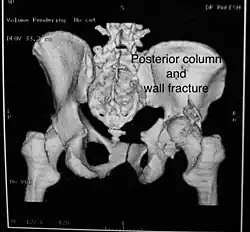

Posterior column and wall fracture as seen on 3D CT -